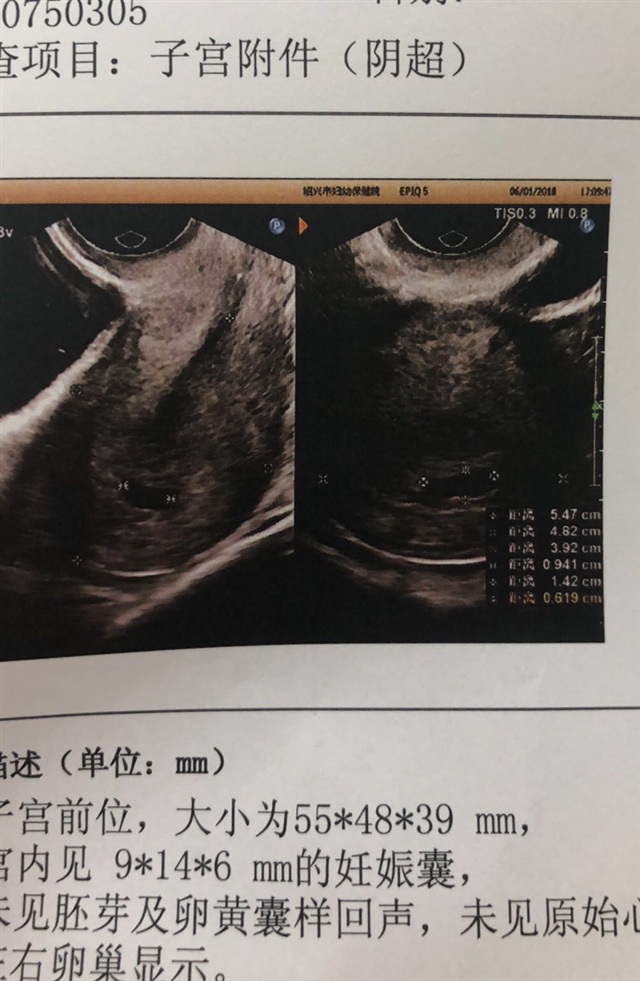

未见胚芽及卵黄囊样回声。应该不到6周吧,4.5周的样子。。